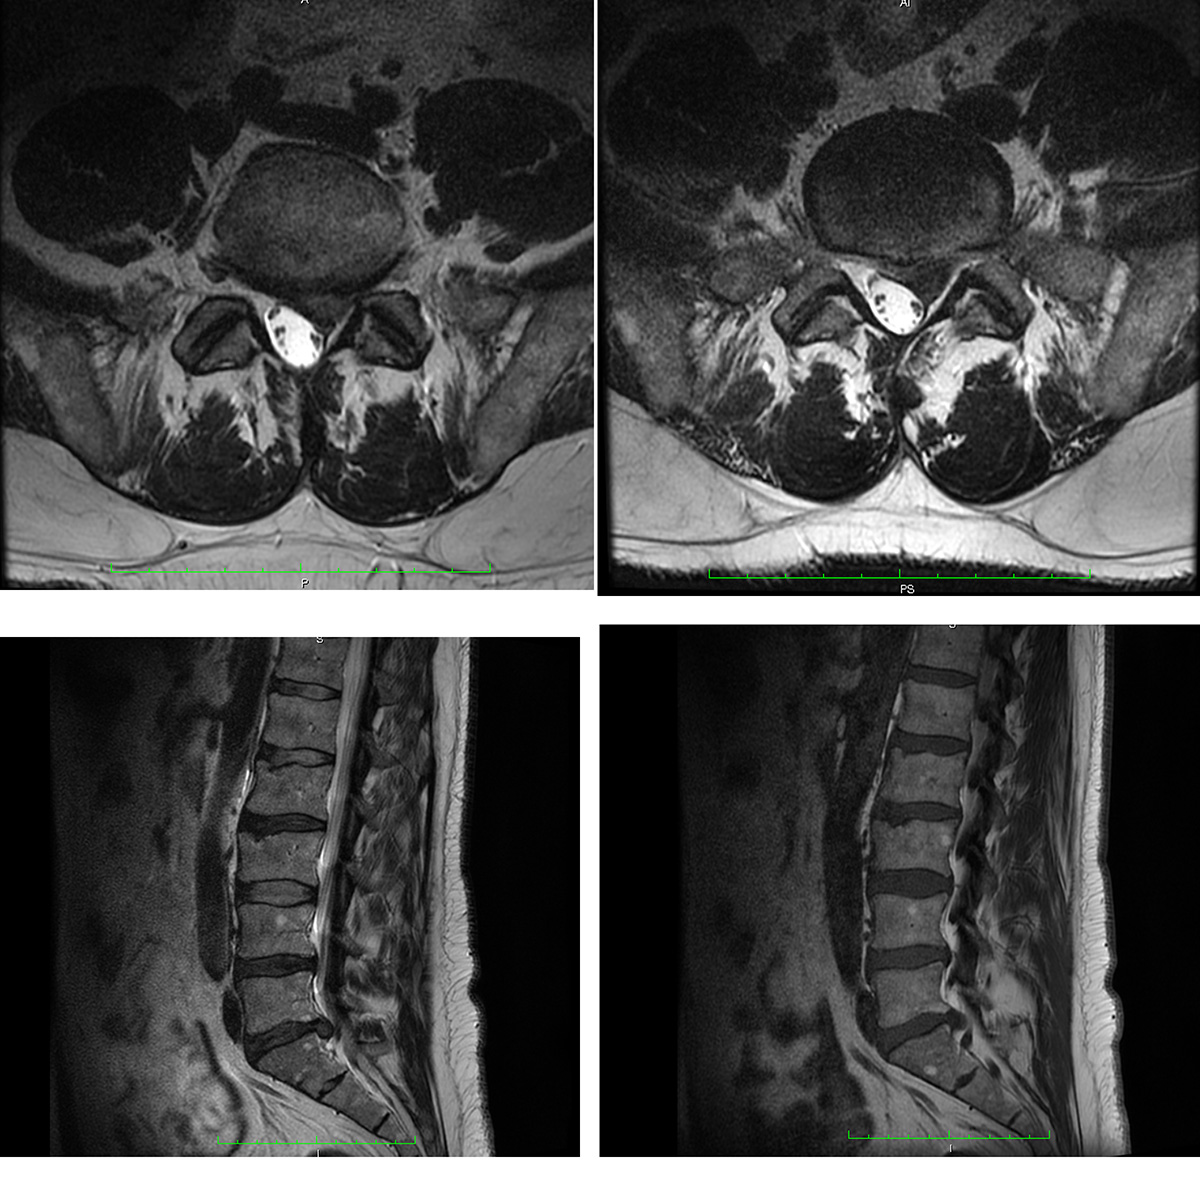

MRT Bilder LWS erste Einschätzung?

Wer kann mir etwas zu meiner LWS sagen? (Bandscheibenvorfall, MRT Befund)

Wer kann mir diese MRT Aufnahmen der LWS auswerten ? (Wirbelsäule, Befund)